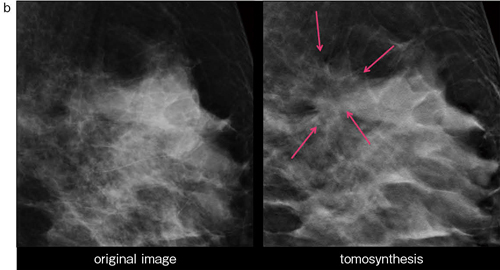

■症例2:40歳代後半,女性。5年前に葉状腫瘍に対して摘出術施行。

a:左右MLO画像

b:右MLO画像(左),トモシンセシス画像(右)

「特に構築の乱れについては,大きくても2D画像では見えないこともよくありますが,トモシンセシスでは引きつれの様子がはっきりとわかります。また,2D画像では,カテゴリー分類の決定に迷うこともあるのですが,それを明確にできることも非常に有用です」